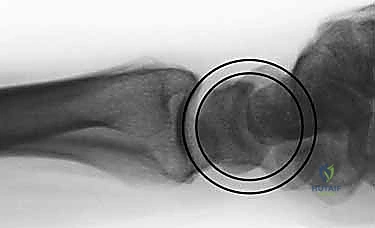

- الأشعة السينية (X-rays):

هي الخطوة الأولى لتقييم الكسر. يتم أخذ صور من زوايا متعددة (أمامية خلفية، جانبية، ومائلة) لتحديد موقع الكسر الأساسي ودرجة الانزياح والتقصير في عظم الكعبرة.

- التصوير المقطعي المحوسب (CT Scan) مع إعادة البناء ثلاثي الأبعاد:

هذا هو المعيار الذهبي الذي يعتمده الدكتور هطيف لجميع كسور المفصل المعقدة. تتيح الأشعة المقطعية رؤية كل شظية عظمية بوضوح تام، وتحديد حجمها، وموقعها، ودرجة تفتت السطح المفصلي بدقة ملليمترية. من خلال إعادة البناء ثلاثي الأبعاد (3D Reconstruction)، يمكن للدكتور هطيف "رؤية" الكسر من جميع الزوايا قبل فتح الجلد، مما يسمح له باختيار الغرسات (الصفائح والمسامير) الدقيقة لكل شظية وتحديد المداخل الجراحية المثلى.